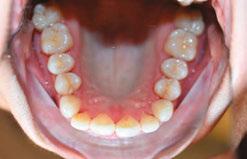

Patient J, a 39-year-old female, (Figures 1, 2, 3, 4, 5, 6) came to the office with concerns about difficulties chewing food and experiencing dry mouth upon waking up in the morning. Additionally, her partner was disturbed by her snoring. Upon examination, several issues came to light:

1. An open bite in the anterior region and a posterior crossbite

2. Breathing through the nose 10% of the time.

3. Lips and cheek muscles actively helping with swallowing food and drinks

4. Lips open 100% of the time

5. Tongue cannot maintain position on a spot, moves between teeth upon swallowing

6. Tongue thrust

7. Weak control over soft palate

Muscle tension around the temporomandibular joint (TMJ) was also evident5 as well as mandibular bilateral lingual torus as response to constant occlusal pressure applied during bruxism.

Figures 5 and 6: 5. Upper arch before treatment. 6. Lower arch before treatment